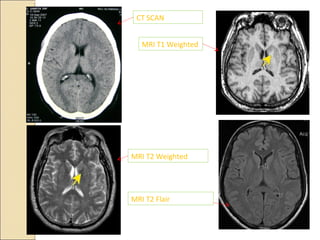

CT SCAN

MRI T1 Weighted

MRI T2 Weighted

MRI T2 Flair